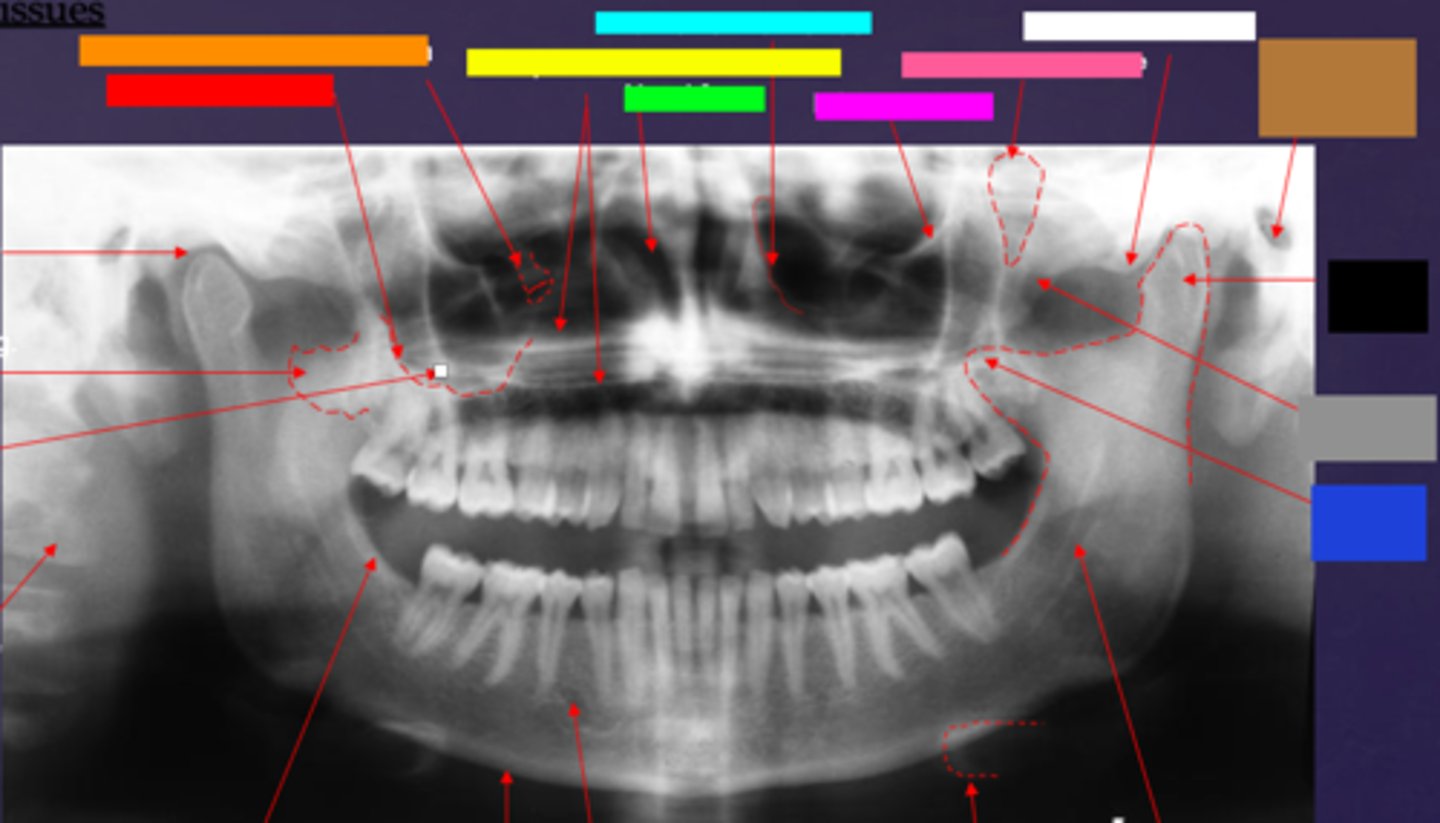

ID the hard tissue anatomy indicated by the arrow pointing from the red box:

floor of max. sinus

ID the hard tissue anatomy indicated by the arrow pointing from the orange box:

infra orbital canal and foramen

ID the hard tissue anatomy indicated by the arrow pointing from the yellow box:

hard palate/floor of nasal fossa

ID the hard tissue anatomy indicated by the arrow pointing from the green box:

nasal fossa

ID the hard tissue anatomy indicated by the arrow pointing from the light blue box:

ant. wall of max. sinus

ID the hard tissue anatomy indicated by the arrow pointing from the dark blue box:

coronoid process

ID the hard tissue anatomy indicated by the arrow pointing from the hot pink box:

infra orbital rim

ID the hard tissue anatomy indicated by the arrow pointing from the pink/salmon box:

pterygomaxillary fissure

ID the hard tissue anatomy indicated by the arrow pointing from the brown box:

external auditory meatus/ear canal

ID the hard tissue anatomy indicated by the arrow pointing from the white box:

articular eminence

ID the hard tissue anatomy indicated by the arrow pointing from the black box:

mandibular condyle

ID the hard tissue anatomy indicated by the arrow pointing from the gray box:

zygomatic bone

mandibular fossa